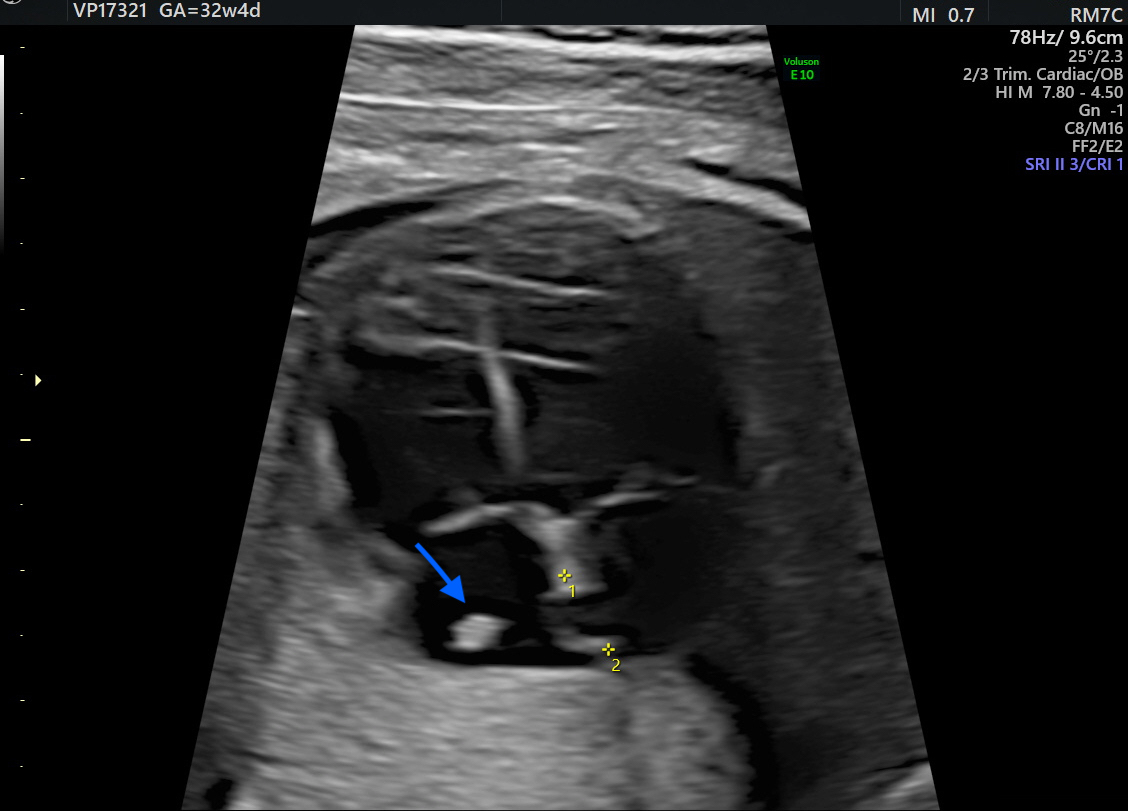

Figure 3. Postanatal apical 5-chamber view: echocardiography at 72 h of age displayed a persistent hyperechoic mass (arrow) within the right atrium compatible with hypertrophic crista terminalis. The structure showed no variations in growth compared to previous scans. RA: right atrium; RV: right ventricle; LA: left atrium; LV: left ventricle; AO: ascending aorta.

At 72 h of life, postnatal transthoracic echocardiography demonstrated a persistent hyperechoic mass in the right atrium, not grown and not modified compared to previous scans, and interpreted as HCT. There was no evidence of right atrial inflow obstruction, and no mass growth was observed (Figure 3).